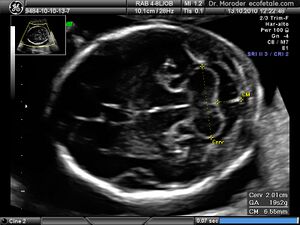

Ultrasound image of the fetal head at 19 weeks of pregnancy in a modified axial section, showing the normal fetal cerebellum and cisterna magna

Congenital malformation, hereditary disorders, and acquired conditions can affect cerebellar structure and, consequently, cerebellar function. Unless the causative condition is reversible, the only possible treatment is to help people live with their problems.[21] Visualization of the fetal cerebellum by ultrasound scan at 18 to 20 weeks of pregnancy can be used to screen for fetal neural tube defects with a sensitivity rate of up to 99%.[22]